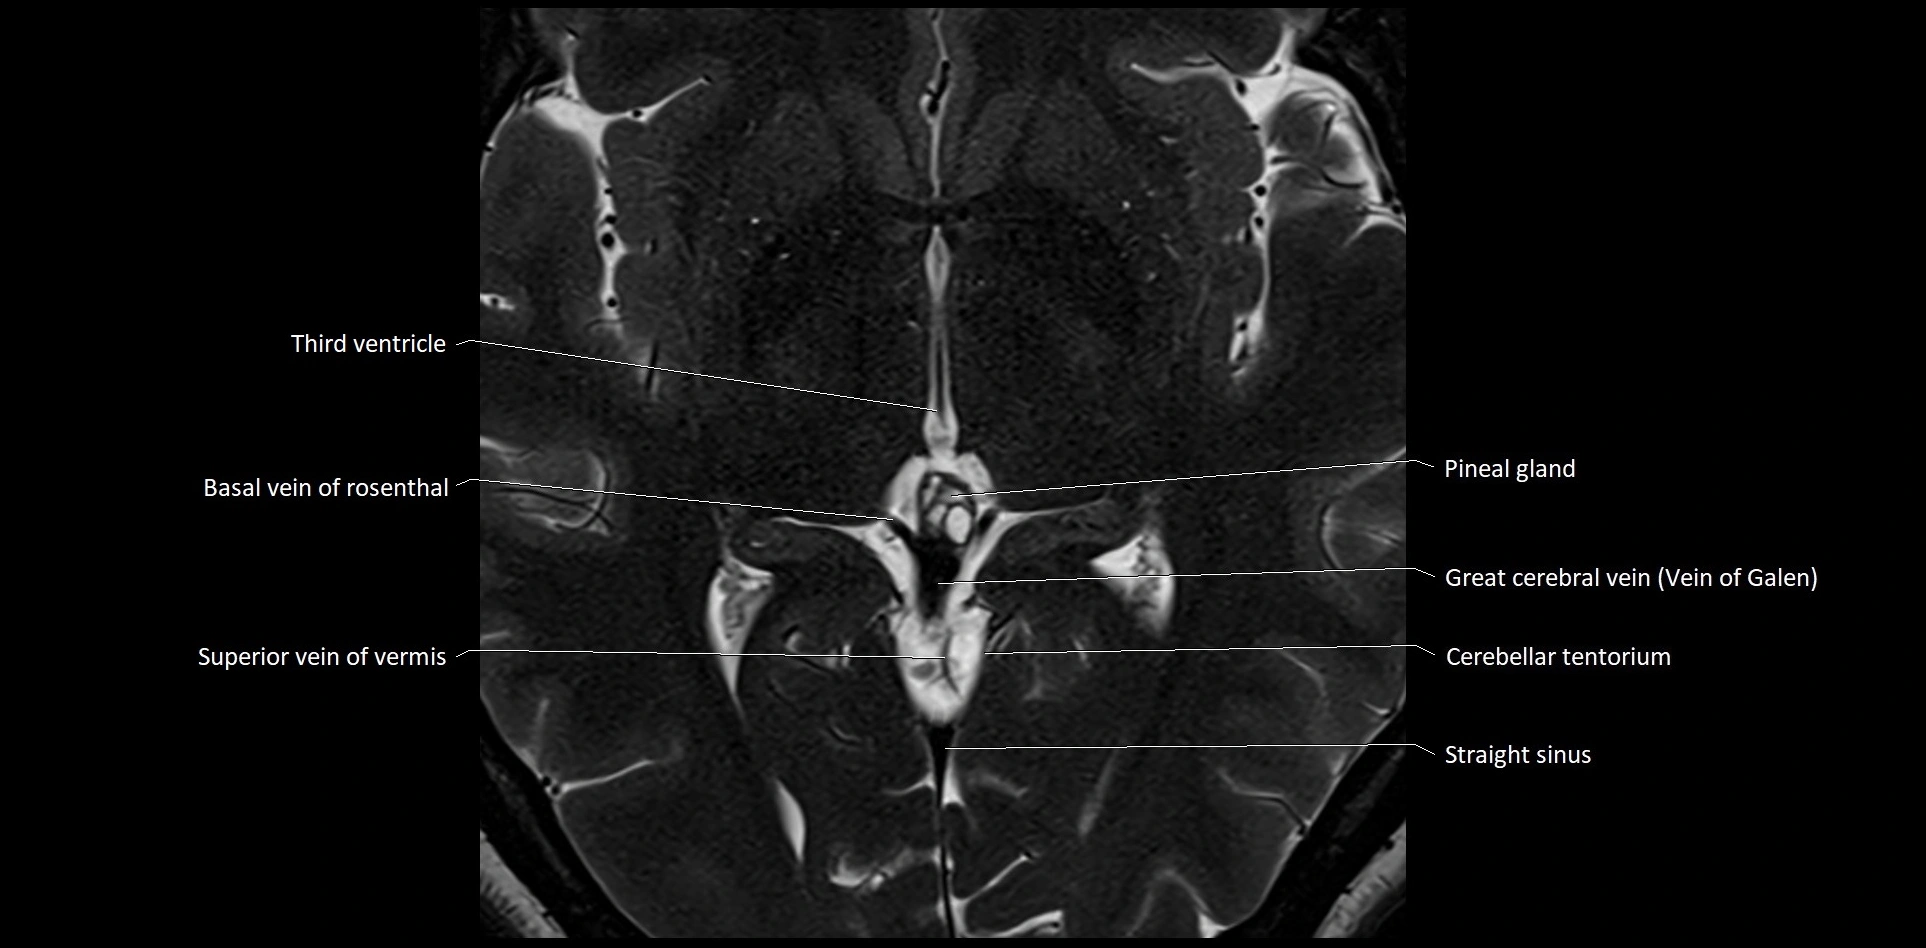

- Internal cerebral vein

- Pineal gland

- Straight sinus

- Superior vein of vermis

- Transverse sinus